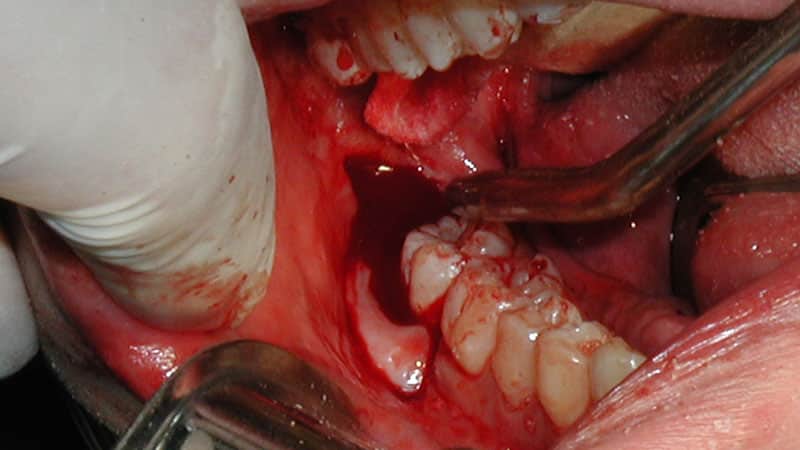

При сложном удалении зубов мудрости хирург применяет бормашину, выполняет разрезы и сшивает раны. Обычно такая операция требуется для ретинированных или горизонтально расположенных зубов. Врачам часто необходимо удалить часть кости, чтобы получить доступ к зубу и его корням.

Процедура проводится с использованием мощных обезболивающих в условиях хирургического кабинета. Все необходимые антисептические меры обеспечивают стерильность помещения. Через три дня после операции рану зашивают рассасывающимися нитями, которые удаляются только после полного заживления.

Удаление зубов мудрости – это сложная и специфическая процедура, в ходе которой хирург выполняет операцию с использованием специальных щипцов. Перед началом вмешательства пациенту вводят анестезию, после чего врач делает разрез на десне и высверливает небольшую лунку в костной ткани.

Если это необходимо, зуб может быть распилен на части с помощью стоматологического диска или бор. Затем в альвеолярное отверстие помещается лекарственное средство, и рана зашивается. Эта операция считается максимально безопасной, так как она снижает риск травмирования слизистой оболочки, соседних зубов и костных тканей.